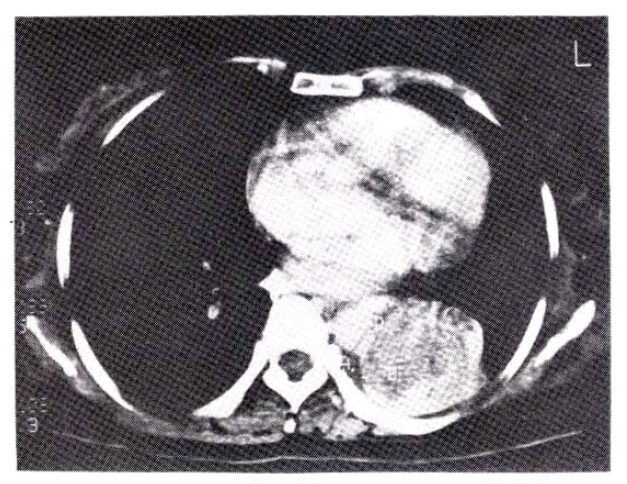

Five weeks before admission she began to cough up blood-streaked sputum. In a recumbent position she suffered from mild dyspnea and wheezing respiration intermittently. Ten days before admission she coughed up frank blood. At the time of admission, the physical examination revealed wheezing and decreased breath sounds in the left lower lung field. Mucocutaneous lesions and palpable lymph nodes were not present. Chest roentgenogram showed left lower lobe collaps (Fig. 2). Laboratory data were normal except for lactic dehydrogenase (LDH) of 414 IU/L. Liver scan was normal. Four repeated sputum cytologic examinations were negative for malignant cells. Pulmonary function tests showed a moderate restrictive pattern. On bronchoscopy, a fungating, dark grayish, irregularly surfaced endobronchial mass at the orifice of the left lower lobe bronchus nearly completely occluding the lumen (Fig. 3) was found. Bronchoscopic biopsy revealed metastatic malignant melanoma (Fig. 4). Computed tomography of the chest showed left lower lobe collapse and aortic invasion (Fig. 5). So palliative chemotherapy with dimethyl triazeno imidazole carboxamide (DTIC) was given as a five day schedule and she was discharged.